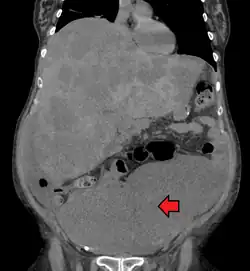

Medical imaging

A colorectal cancer is sometimes initially discovered on CT scan.[95]

The presence of metastases is determined by a CT scan of the chest, abdomen, and pelvis.[20] Other potential imaging tests such as PET and MRI may be used in certain cases.[20] MRI is particularly useful to determine the local stage of the tumor and to plan the optimal surgical approach.[95]